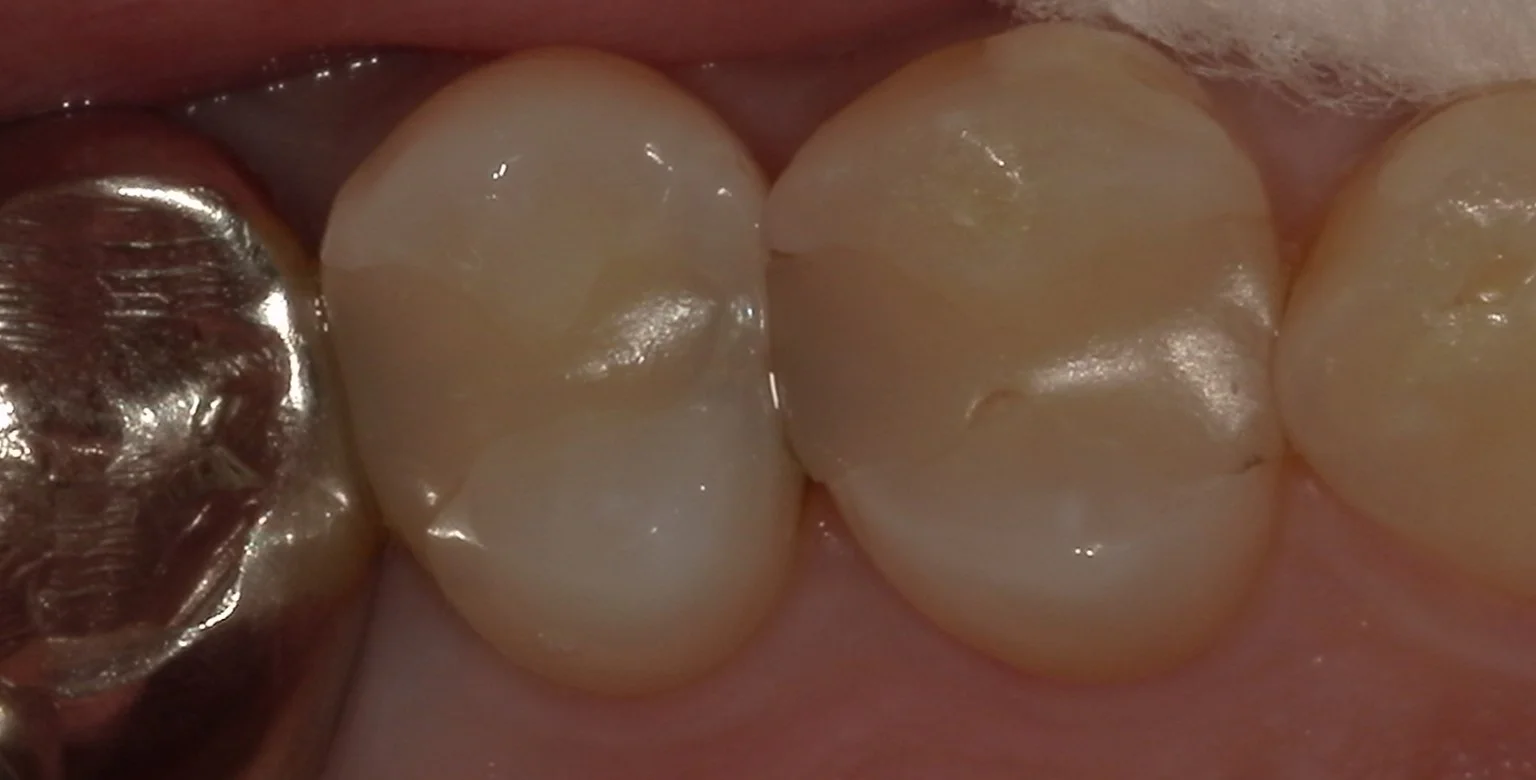

まずは術前。

元々保険内のコンポジットレジンで治療されている歯ですが、

画面右側と左側の歯の間が少し黒っぽくなっているのが分かりますかね?